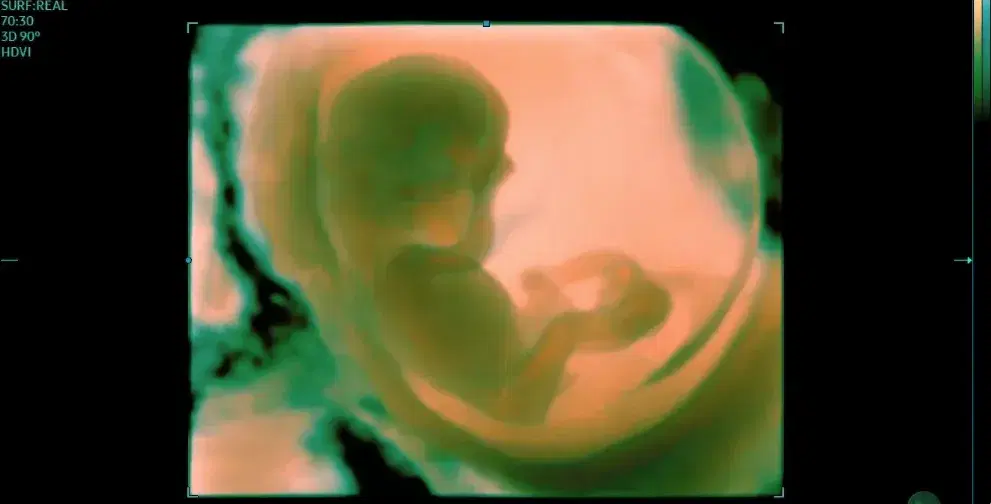

Fetal Ultrasound Course